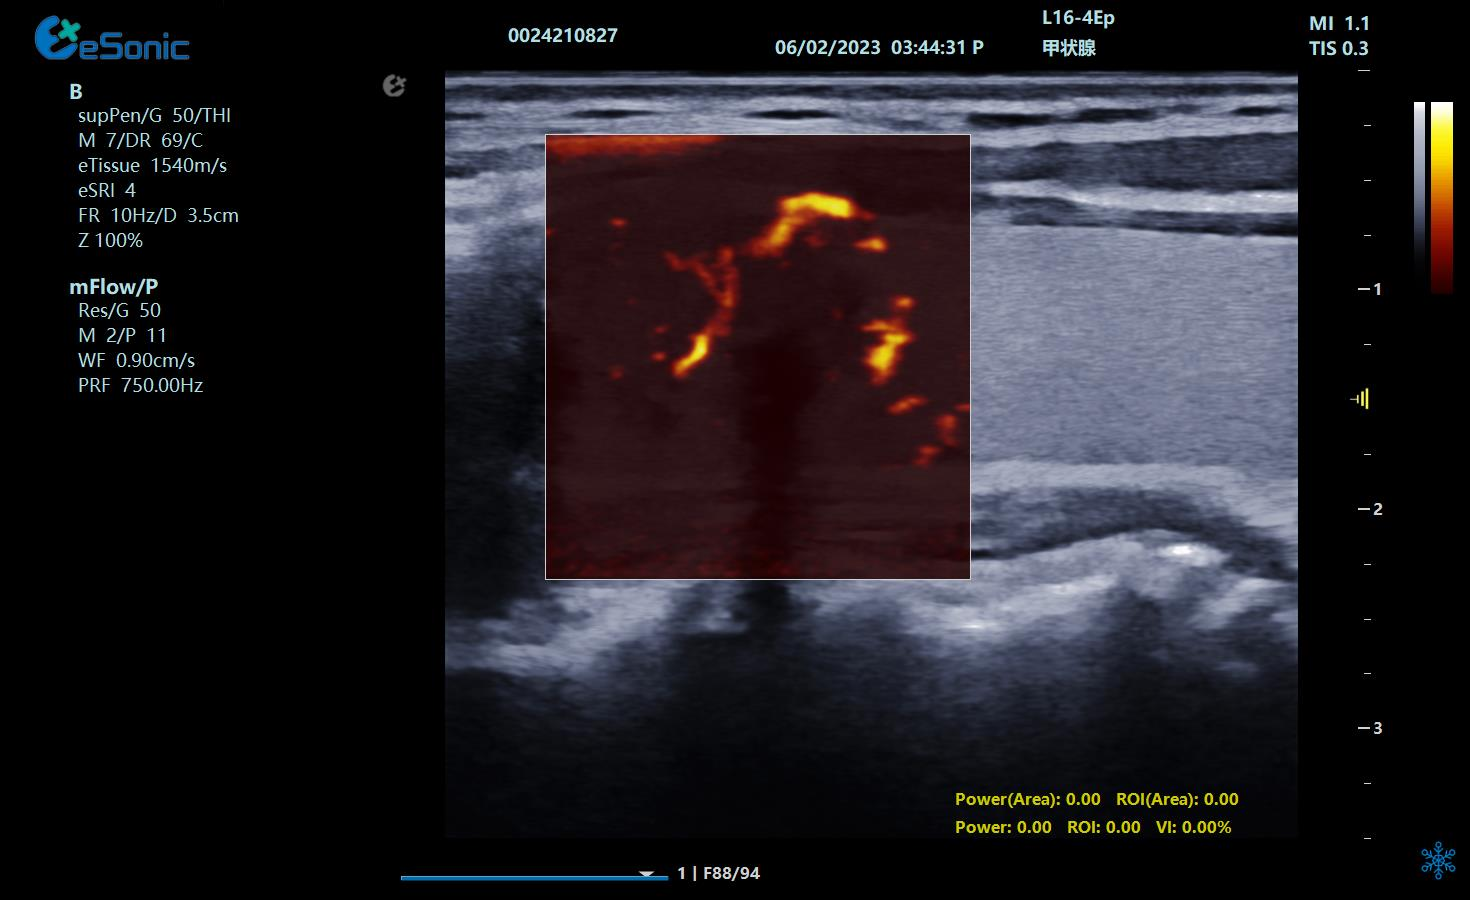

甲状腺乳头状癌微血流